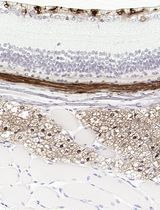

Fluoro-Jade is a fluorescent derivative used for histological staining of degenerating neurons. This technique is simple and sensitive enough to label distal dendrites, axons, axon terminals as well as neuronal bodies. Fluoro-Jade has excitation and emission peak of 480 and 525 nanometer respectively. It can be visualized using a fluorescein/FITC filter. Some reports have demonstrated that Fluoro-Jade can also be useful to detect glial cell death (Anderson et al., 2013; Damjanac et al., 2007).

Figure 2. FJB-positive neurons in the mouse cerebral cortex following ischemic stroke